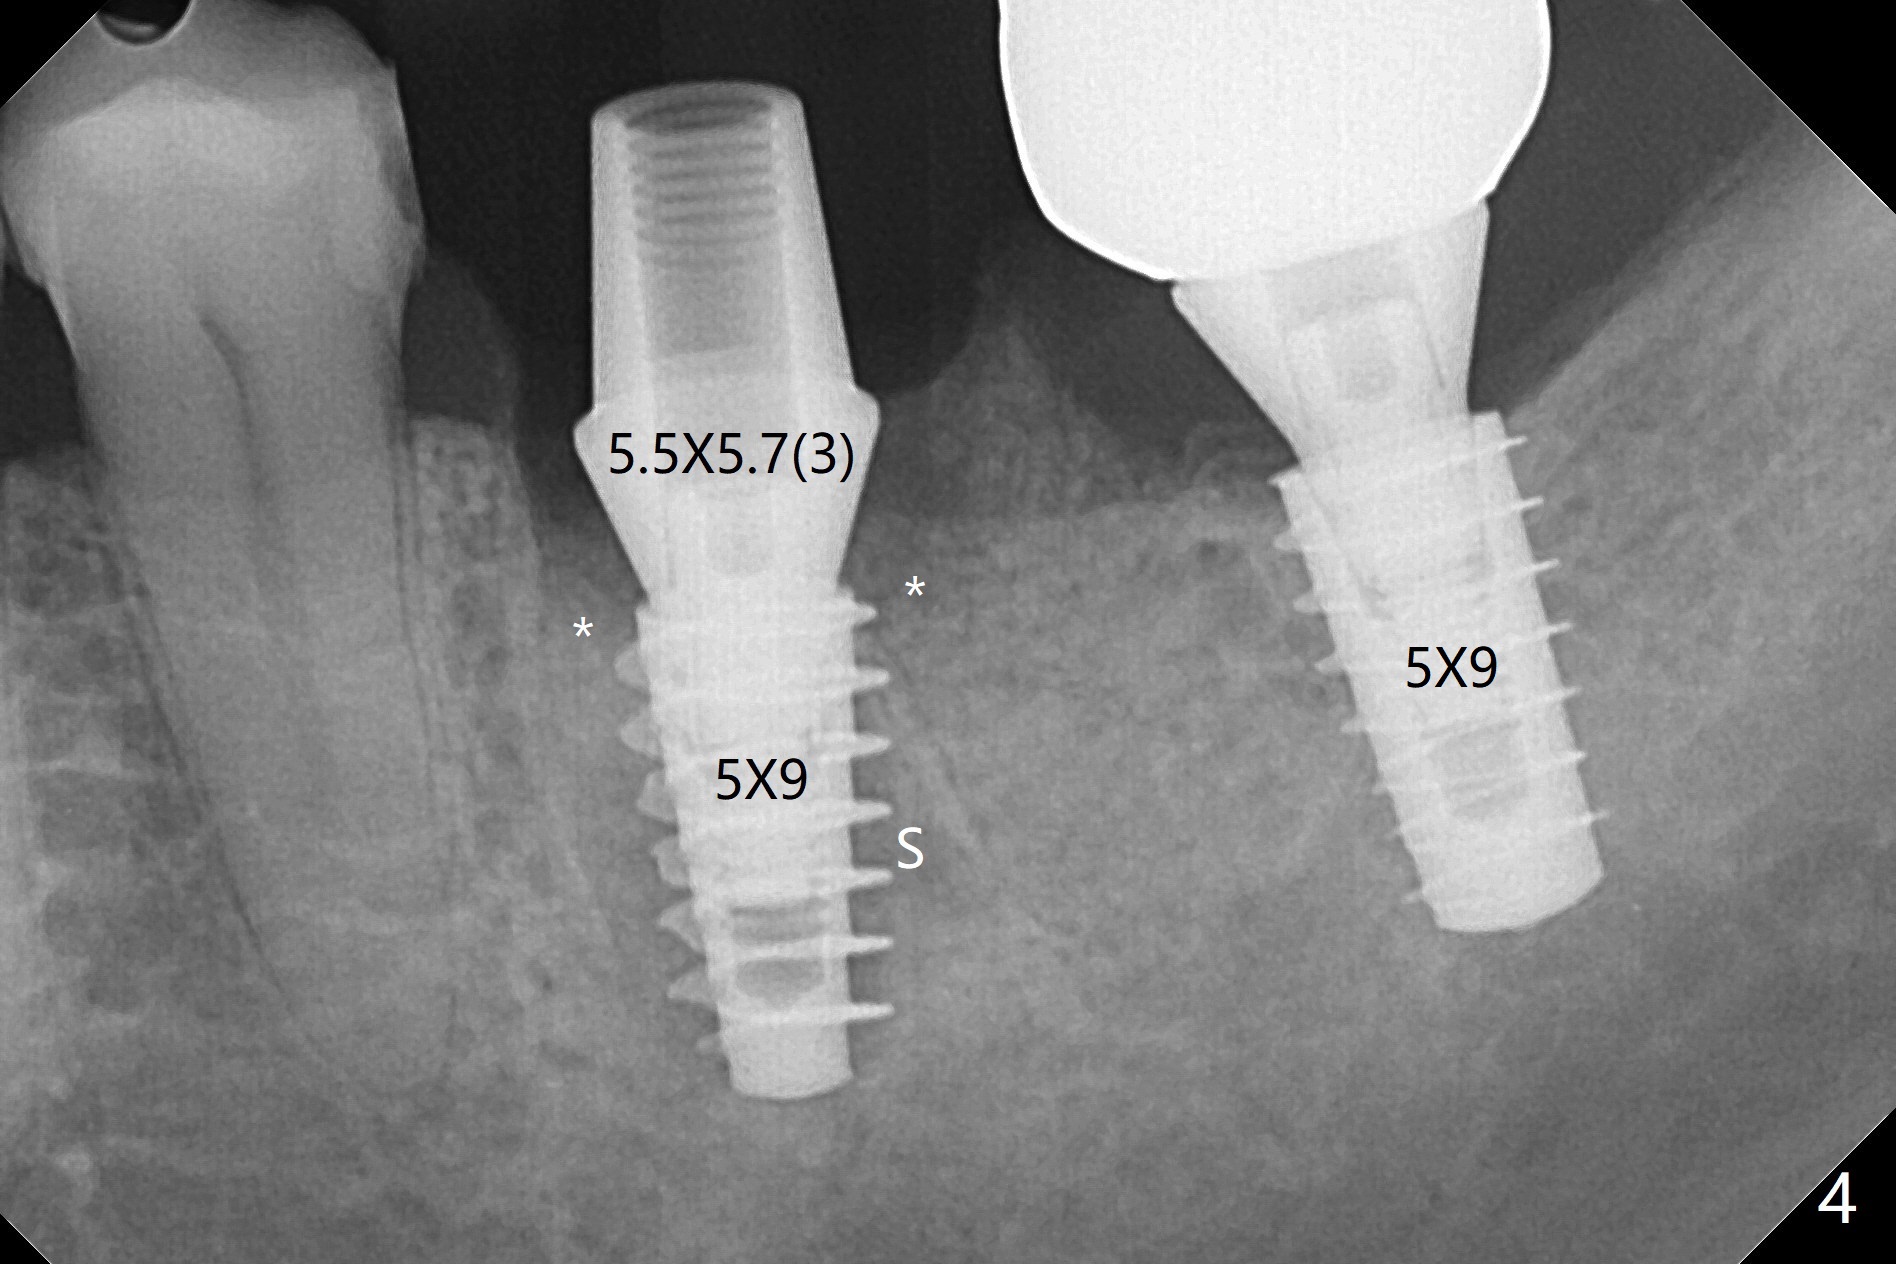

Venopuncture is conducted (Fig.1) for PRF and sticky bone (cortical chip and .5 cc ß-TCP). After use of proximators at #19, cowhorn forceps are applied, resulting in metal crown dislodgement. Since there is distal bone loss, distal socket sheath is contemplated. The tooth is sectioned. When an elevator is inserted between the roots, the distal root is loosened first. The 2 roots are removed, revealing a rounded end septum (Fig.2 S) and a larger distal socket. To avoid osteotomy deviation over the septum, a 12 mm bone trimmer is used, followed by point drill (Fig.3 *). But the lower half of the implant is deviated mesial (Fig.4) with decreased torque (~ 10 Ncm). To overcome this misfortune, the roots should not be removed until osteotomy is finished. Dual zones of bone graft is conducted. Sticky bone is placed until the plateau of the implant with a healing screw in place (Fig.4 * (bone zone)). After placement of a pair abutment, the same bone graft is packed until the margin of the abutment (Fig.5 * (soft tissue zone)). An immediate provisional is fabricated to close the socket with a piece of PRF as well. Fig.6-11 explains why the lower half of the implant deviates to the mesial socket, while Fig.12-16 illustrates how to prevent the deviation. After extraction of #19 (Fig.6,7), the crest of the septum is flattened (Fig.8 arrowhead) to prevent the initial deviation (Fig.9 red line). When a drill reaches a space (a socket, mesial in this case), the drill is deflected to the least resistant area (Fig.10 a bent red line), leading to the implant deviation apically (Fig.11 green). To prevent the apical deviation, therefore, the roots of the affected tooth is temporarily not removed (Fig.12). The osteotomy should not deviates with surgical guide because of similar density between the tooth and the bone (Fig.13). When the osteotomy is finished (Fig.14), the roots are extracted (Fig.15). The implant to be placed should not have deviation (Fig.16 green). The papillae are maintained by the immediate provisional 11 days postop (Fig.17). The incompletely seated abutment at #18 (Fig.5 <) is reseated completely 6 months postop (Fig.18). Crestal bone forms distal to #19 implant. There is no bone loss 4 months and 3 years 1 month post cementation at #19 and 18, respectively (Fig.19,20).